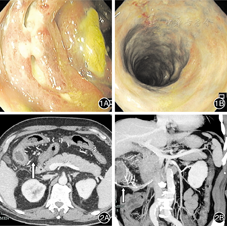

患者男,74岁,因"右侧腹部疼痛1个月,发热1 d"于2019-03-17入院浙江省衢州市人民医院。患者1个月来持续性腹部隐痛,右下腹为主,大便不成形,色黄,入院1 d前出现发热,达38.6℃,无畏寒。饮酒史40余年,日饮中药酒"五加皮酒"200 mL。入院查体:血压150/73 mmHg(1 mmHg=0.133 kPa),腹软,右侧腹压痛明显,无反跳痛,肝脾肋下未及,双下肢无凹陷性水肿。实验室检查:血红蛋白127 g/L,白细胞计数7.6×109/L,血沉55 mm/h,C-反应蛋白101.52 mg/L,血清白蛋白31.6 g/L,球蛋白35.5 g/L,血清降钙素原0.63 ng/mL;大便隐血(+);肝炎系列、肿瘤标志物检查均无异常,结核抗体阴性。心电图正常。腹部超声:肝、胆、胰腺未见异常。结肠镜检查:肠腔黏膜充血水肿、灰暗,糜烂从回盲部至乙状结肠均有,升、横结肠皱襞消失,溃疡附着有脓性分泌物(图1)。肠镜活检病理:(升结肠)黏膜慢性炎伴坏死。腹部CT平扫:升、横结肠管壁明显增厚水肿,四周脂肪间隙模糊,系膜血管钙化,考虑缺血性肠病。门静脉CT血管成像:门静脉主干走形正常,管腔内无充盈缺损影;右半结肠静脉管壁见多发点状、细条状钙化影,相应结肠管壁增厚,考虑为静脉硬化性肠炎(图2)。入院后予抗炎,丹参川芎嗪注射液、前列地尔注射液改善微循环等治疗。次日热退,腹痛逐渐好转,复查C-反应蛋白14.90 mg/L,谷丙转氨酶18.3 U/L,血清降钙素原0.22 ng/mL。住院8 d出院。出院诊断:特发性肠系膜静脉硬化性肠炎(idiopathic mesenteric phlebosclerosis,IMP)。嘱戒酒。电话随访,患者未戒酒,时有腹部隐痛,大便稀糊。出院26 d因"突发腹痛5 h余"急诊入院。查体:痛苦面容,腹肌明显紧张,显著压痛,伴反跳痛,以右侧腹部为著,听诊肠鸣音未闻及。急诊全腹部CT平扫:膈下及上腹腔游离气体,消化道穿孔考虑;结肠肝曲肠壁增厚,四周有明显渗出,周围系膜血管多发钙化(图3)。实验室检查:C-反应蛋白126.62 mg/L。急诊手术:切开腹膜见腹腔淡血性积液及气体逸出,积液100~120 mL,探查见盲肠向升结肠方向明显弯曲,升结肠偏下方结肠破裂,破口大小约3.5 cm,间断有大便自破口溢出,升、横、降结肠广泛发黑、挛缩、水肿,其中以升结肠为著,伴多发性地图样坏死灶。行右半结肠切除和回肠造瘘术。大体病理:见切除右半结肠肠管长26 cm,近回盲部肠管增粗,最大径7.5 cm;剪开肠管有大量粪便潴留,皱襞消失,结肠肠壁增厚,浆膜面暗红色。镜检病理:(右半结肠)黏膜慢性炎伴出血,肠血管壁增厚、玻璃样变及钙化(图4),部分肠壁伴坏死;(肠周)14只淋巴结慢性炎。术后5个月后再次行结肠次全切除术加回肠造瘘回纳术,随访至今5个月,局部继发肠瘘,一般状况良好。

本例在确诊IMP后1个月出现结肠自发性穿孔破裂,紧急剖腹手术见盲肠向升结肠方向弯曲,升结肠偏下方结肠破裂,破口大小约3.5 cm,伴多发性地图样坏死灶。病理示肠血管壁增厚、玻璃样变及钙化,部分肠壁伴坏死。复习文献该病有少数肠坏死手术报告[1,9],但未见有结肠自发性穿孔至破裂。回顾患者结肠镜图像显示升、横结肠蓝色的水肿黏膜,溃疡深凿相邻而且有脓苔、粪质附着,肠皱襞消失;手术探查见盲肠向升结肠方向弯曲压迫,使此段结肠在肠系膜静脉广泛钙化基础上,静脉淤血、肠壁缺血加重,造成相邻溃疡坏死穿透,形成肠管破裂。此病例罕见,重视对IMP及其少见并发症的认识,及时正确处理是治疗成功的关键。